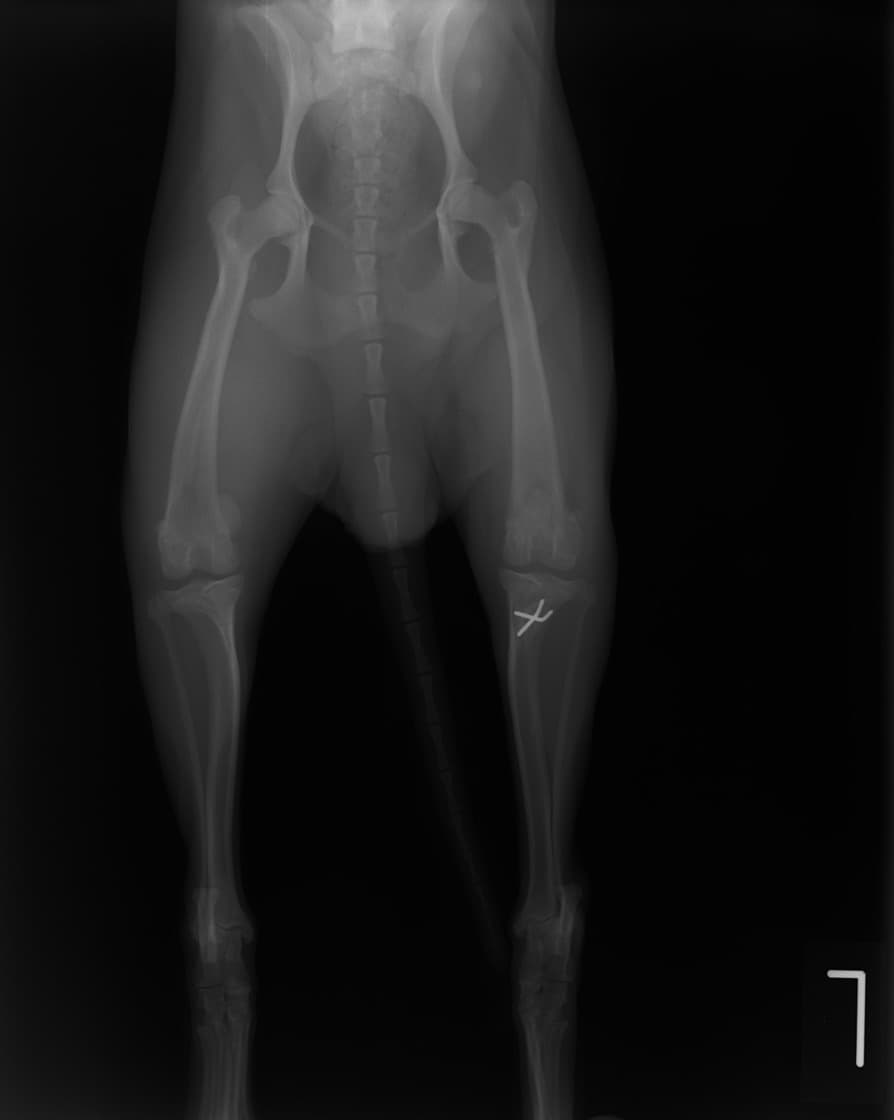

■ 症例20 ポメラニアン 8ヶ月 1.8kg

左右膝蓋骨脱臼 グレードⅢ

2ヶ月前から間欠的跛行が認められ、両膝の膝蓋骨脱臼整復術を行った。

手技は縫工筋及び内側広筋の解放、脛骨粗面の外側転位、滑車ブロック形造溝術、内外側関節包の縫縮を選択し実施した。

右側の膝蓋骨脱臼は上記手技で整復されたものの、左側はそれのみでは膝蓋骨が浮く様子が認められた。その為、PDS縫合糸にて膝蓋靱帯を1糸のみ縫合し、靱帯の縫縮を行った。

膝蓋骨脱臼は膝関節における膝蓋骨の内外側の脱臼と定義されるが、時として単純な内外の脱臼ではなく、膝蓋骨が大きく前方に浮き上がるように脱臼する場合がある。特にトイプードルやポメラニアンといった犬種に多く認められる。

内側脱臼に加えて前方への浮き上がりを矯正する為に、従来より脛骨粗面転移により膝蓋靭帯を外方と下方に引っ張り、固定する方法を選択する。膝蓋骨の前方への浮き上がりが軽度の場合は、従来法ではなく関節包の縫縮で対応していた。しかし、一部の症例で膝蓋骨の動きが悪くなり伸展機構が円滑に機能せずロボット様歩行になるケースがあった。

その為、膝蓋靭帯自体を縫縮する方法を採用した。この方法により、膝関節の伸展機構を妨げず膝蓋骨の軽度の浮きを矯正することが可能となった。

本症例の経過は良好である